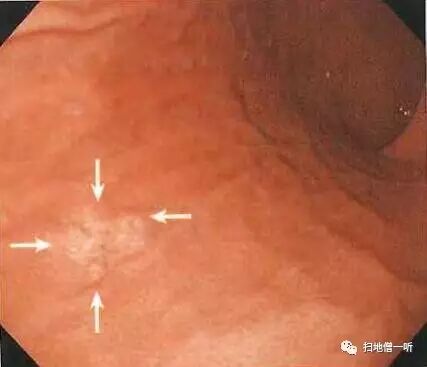

A:胃癌在图3及图6。HP现症感染胃癌。

背景粘膜为O-3型萎缩、肠上皮化生、弥漫性发红。胃体下部前壁可见小片粘膜发红,伴毛细血管扩张。毛细血管扩张常常提示癌性病变,需进行详细观察。正面观察时凸凹感不强。

切线位观察明确其为红色凹陷性病变。

NBI非放大模式下观察可见褐色凹陷区域。

靛胭脂染色后观察可见凹陷区域内胃小区不鲜明化,边界清晰。

抽气后切线位观察凹陷更加明显。

最终诊断:胃体下部前壁,O-IIc,10mm,tub1,T1a(M),UL(-)

小结:发现病变后需要通过改变距离,空气量,角度等进一步详尽观察

扩张的毛细血管伴凹陷考虑癌性病变。

补充:胃体大弯前壁可见粘膜肿胀饱满,点状发红,提示为HP感染。